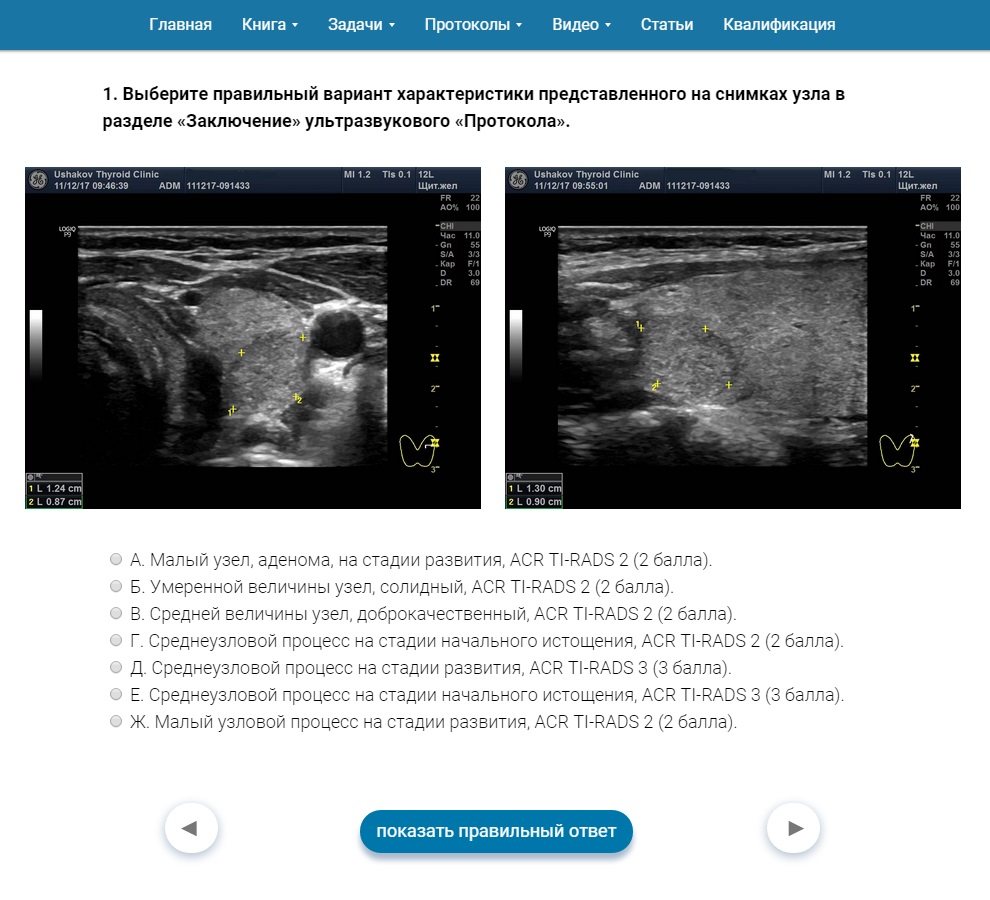

От нашей Клиники создана

Научная школа УЗИ щитовидной железы, где подготовлен курс обучения ACR TI-RADS. Этот курс содержит тесты и примеры УЗИ узлов щитовидной железы по ACR TI-RADS (

рисунок 2).

Рисунок 2 Более 80 теоретических и практических задач по ACR TI-RADS на сайте Научной школы УЗИ щитовидной железы от Клиники щитовидной железы доктора А.В. Ушакова.